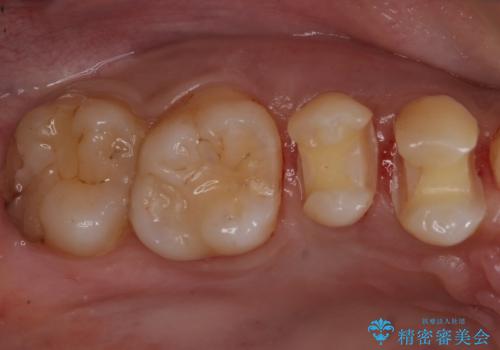

- 歯の健診にて来院。

レントゲンを撮った時にう蝕があったため、拡大鏡下でう蝕が残っていないか確認し

セラミックの詰め物(e-maxインレー)にて治療を行いました。